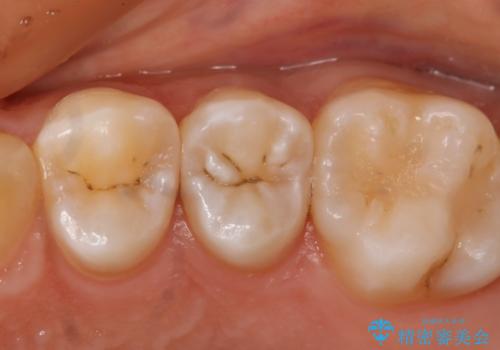

- 左上5番の虫歯治療を主訴に来院された患者様です。

セラミックでの治療を希望されたので形態・切削量を考慮しセラミックインレーでの治療を選択しました。

隣り合っている面(隣接面)は清掃がしづらく虫歯になりやすい場所です。

また、形態の再現が難しいのでインレーなどの補綴物での治療が第一選択となることが多いです。